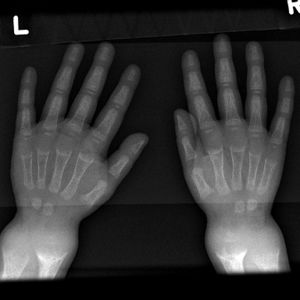

- توسع المعصم[4] raises early suspicion, it is due to metaphysial cartilage hyperplasia.

يصبح اتساع المشاش في المعصمين وعنقي القدم (النهايات السفلية للزند والكعبرة وعظم الفخذ والشظية)، واضحاً للعيان باستمرار الحدثية الرخدية، ويؤدي نقص تكلس العظام خاصة بعد بدء الطفل بالوقوف والمشي إلى تقوسات بالطرفين السفليين وتبدلات في الركبتين فيحدث الروح والفحج.

- شعاعياً: يكون التشخيص الباكر للرخد الفعال أفضل ما يكون في المعصم، لأن التبدلات المميزة في نهاية الزند والكعبرة تحدث في المراحل الباكرة. تتسمك المنطقة الغضروفية ويزداد عرض النهاية البعيدة لجسم العظم، فتبدو متسعة ومقعرة ومهترئة وتنقص كثافة جسم العظم.